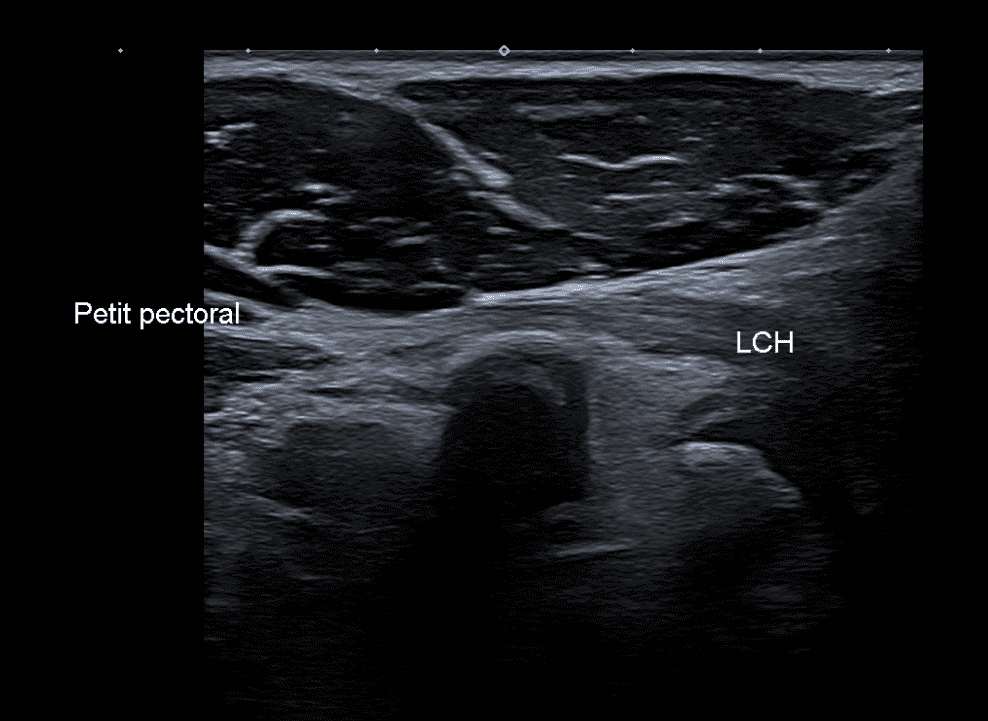

Continuité du petit pectoral avec le ligament coraco-huméral

Continuité anatomique des fibres tendineuses fibrillaires du tendon petit pectoral avec le ligament coraco-huméral, passant en pont au dessus du processus coracoïde.

Dans cette variante, le tendon du petit pectoral (PMT) se prolonge au-delà du processus coracoïde pour s'insérer sur la capsule articulaire gléno-humérale ou d'autres structures adjacentes. Une hypothèse phylogénétique suggère que le ligament coraco-huméral (CHL) pourrait en fait être un vestige du tendon du petit pectoral qui aurait migré de l'humérus vers le processus coracoïde au cours de l'évolution.